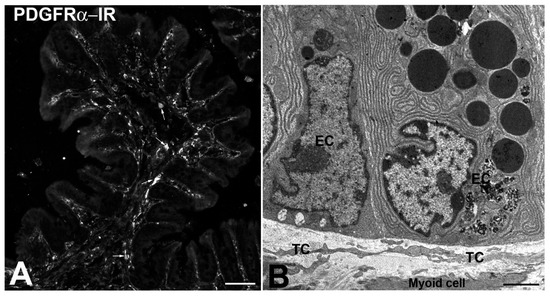

- The TCs might be adult stromal mesenchymal cells able to differentiate in ICCs [16,26]. Notably, while ICCs undergo apoptosis with time, their number does not change significantly in aging [33]. However, images of ICCs mitosis were never seen. Thus, the existence of a pool of stem cells (the TCs?) committed to become ICCs when needed is reasonable. The expression of PDGFRα by the TCs reinforces such a hypothesis since the literature data indicate that PDGF/PDGFR signaling plays critical roles in mammalian organogenesis and morphogenesis [34,35].

- Vannucchi, M.G.; Traini, C.; Manetti, M.; Ibba-Manneschi, L.; Faussone-Pellegrini, M.S. Telocytes express PDGFRα in the human gastrointestinal tract. J. Cell Mol. Med. 2013, 17, 1099–1108. [Google Scholar] [CrossRef]